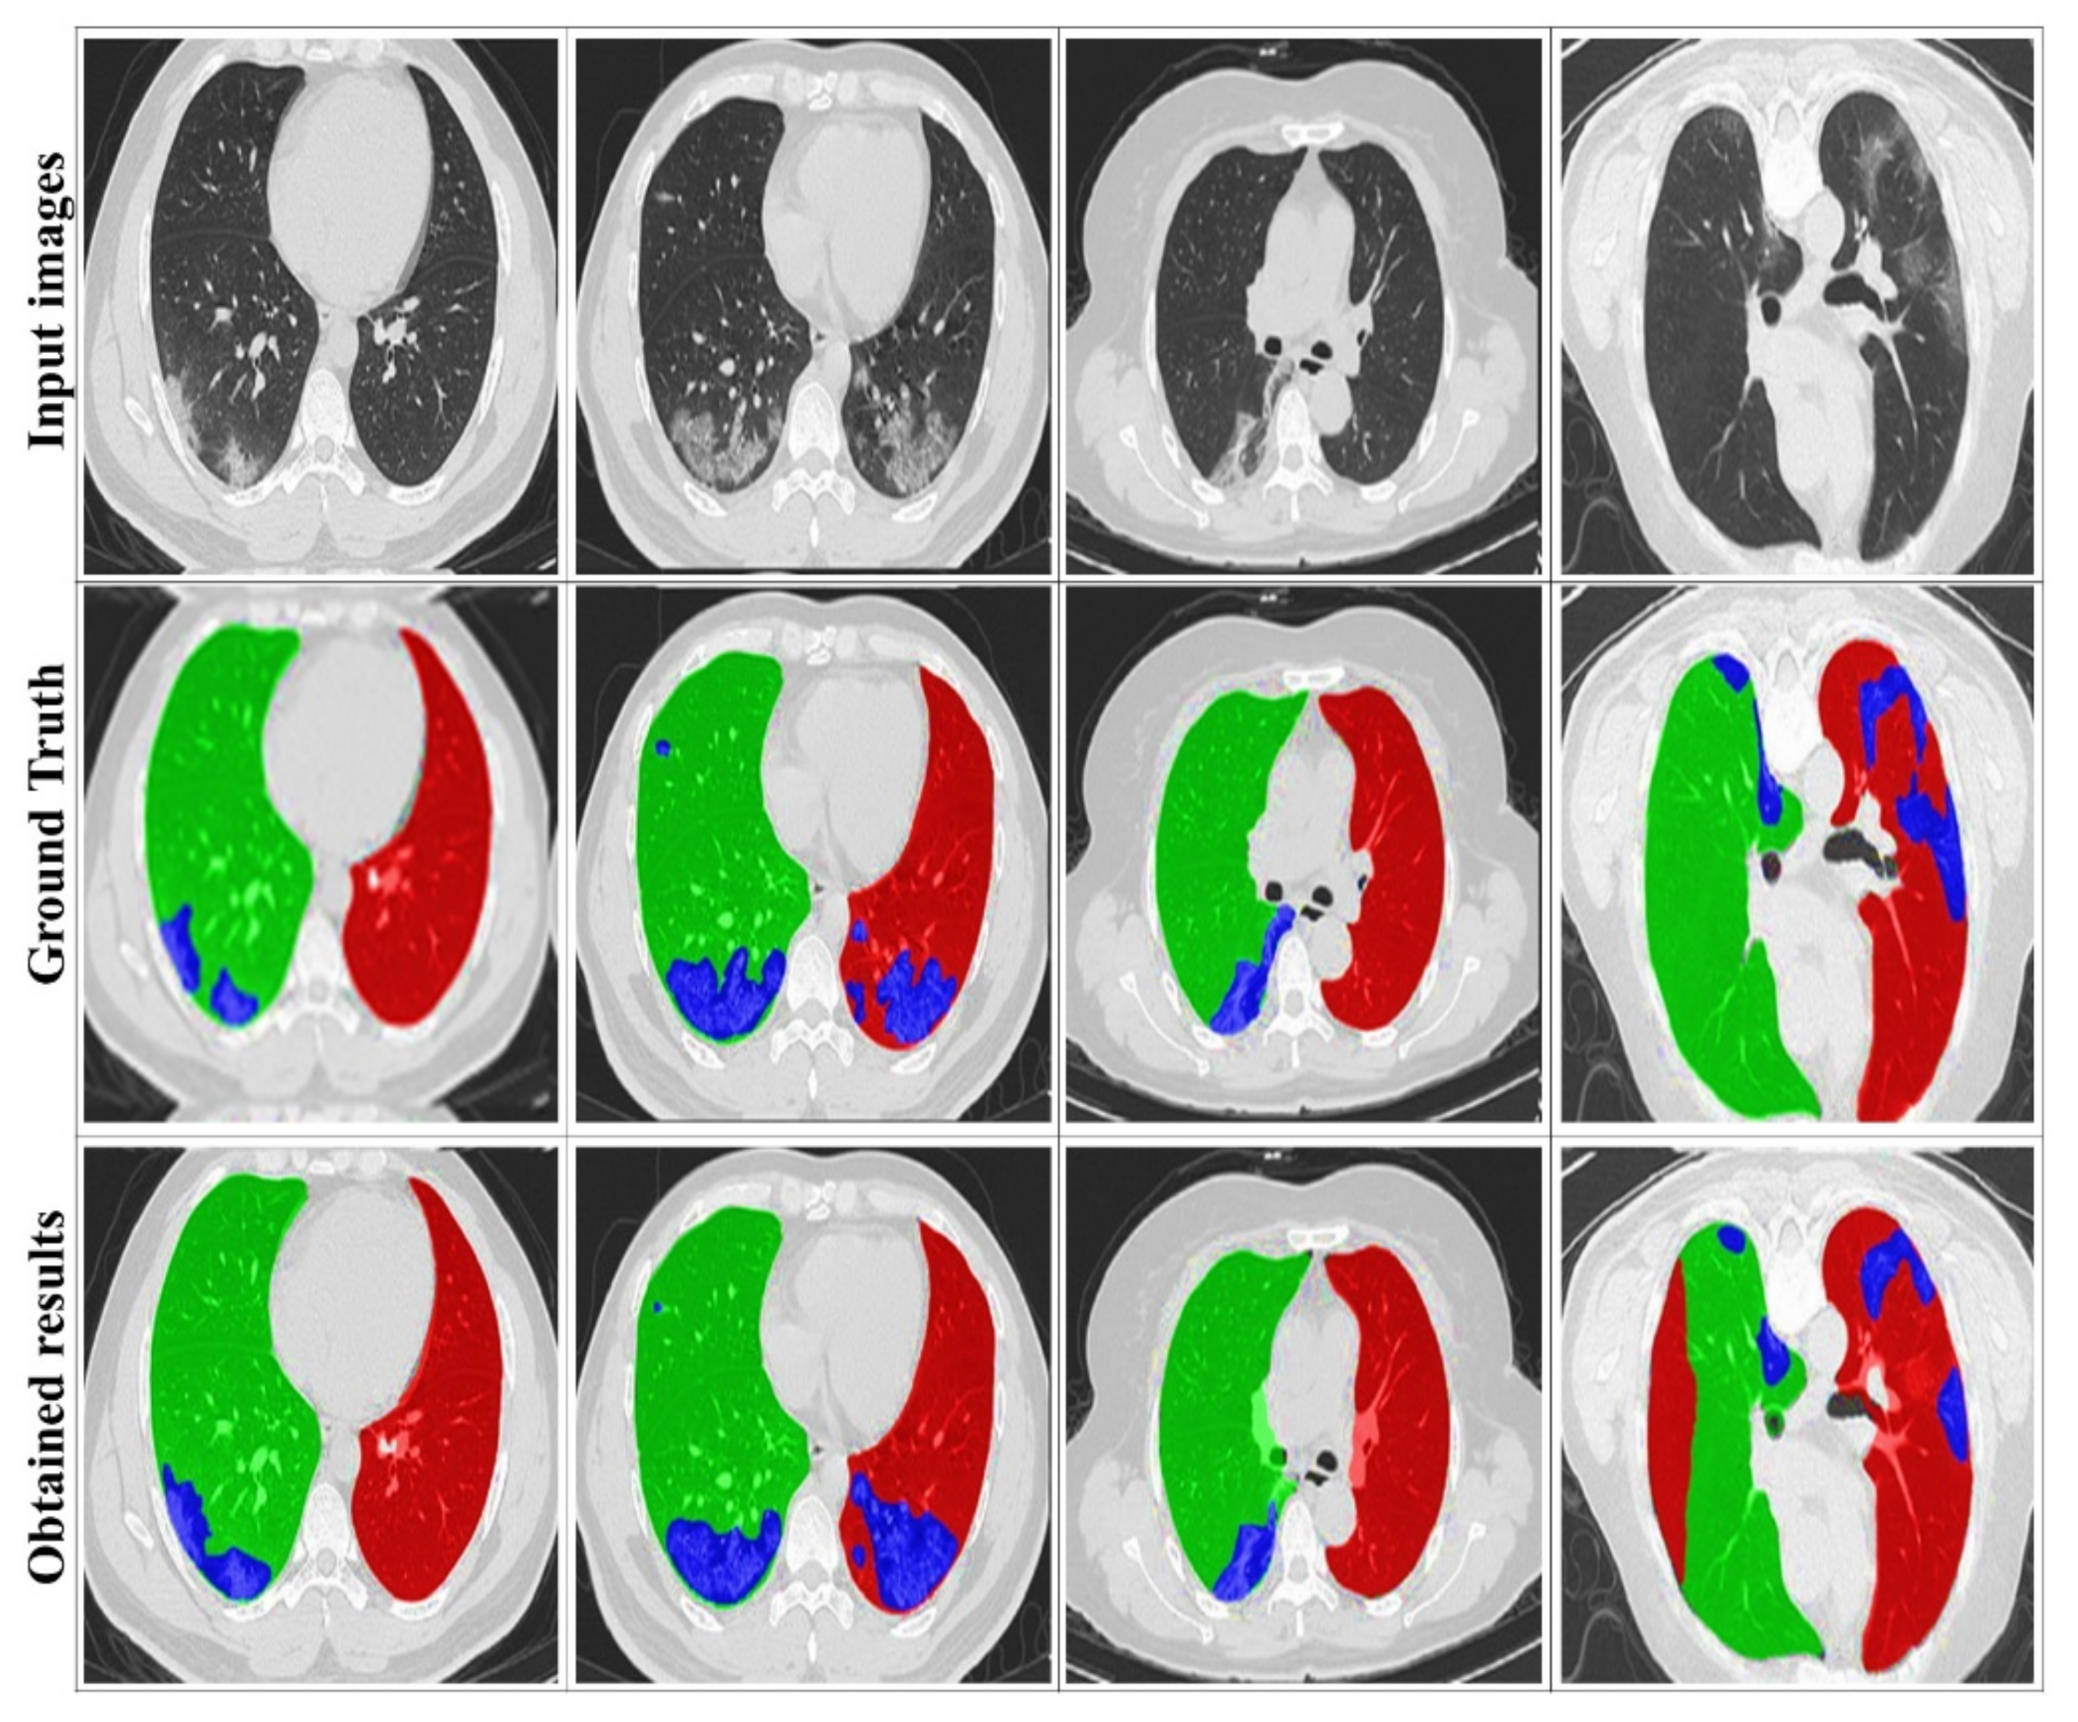

4. Results and Discussion

4.3. Evaluation of the DRL System

4.4. Comparison with State-of-the-Art Methods